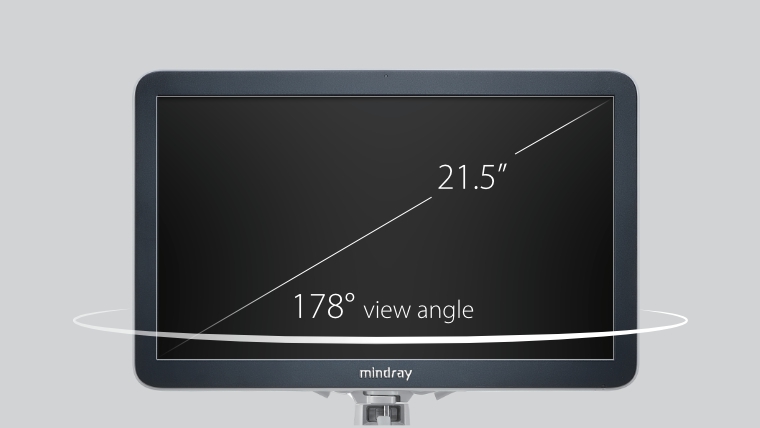

X-Insight es la soluci├│n intuitiva para una mejor visualizaci├│n.

La nueva soluci├│n de Mindray es una excelente transformaci├│n desde la continua comprensi├│n de las necesidades cl├Łnicas del usuario, combinada con la evoluci├│n de la tecnolog├Ła de los ultrasonidos m├Īs puntera. Repleto de vitalidad, con el ├║nico objetivo de visualizar el futuro y evitar los l├Łmites, el ec├│grafo DC-60Exp con X-Insight est├Ī constantemente mejorando con una escalabilidad aumentada. Como un socio personal, el equipo de ultrasonidos DC-60 Exp con X-Insight se centra en lo que verdaderamente importa, ayudando al usuario a administrar su pr├Īctica cl├Łnica con facilidad y seguridad.

Bas├Īndose en una profunda comprensi├│n de las necesidades del usuario, el sistema de ultrasonidos DC-60 Exp con X-Insight est├Ī dise?ado para ofrecer una alta eficiencia con im├Īgenes de precisi├│n, la cual se ve potenciada por una claridad inmediata, una inteligencia excepcional y benefici├Īndose de una c├│moda experiencia.